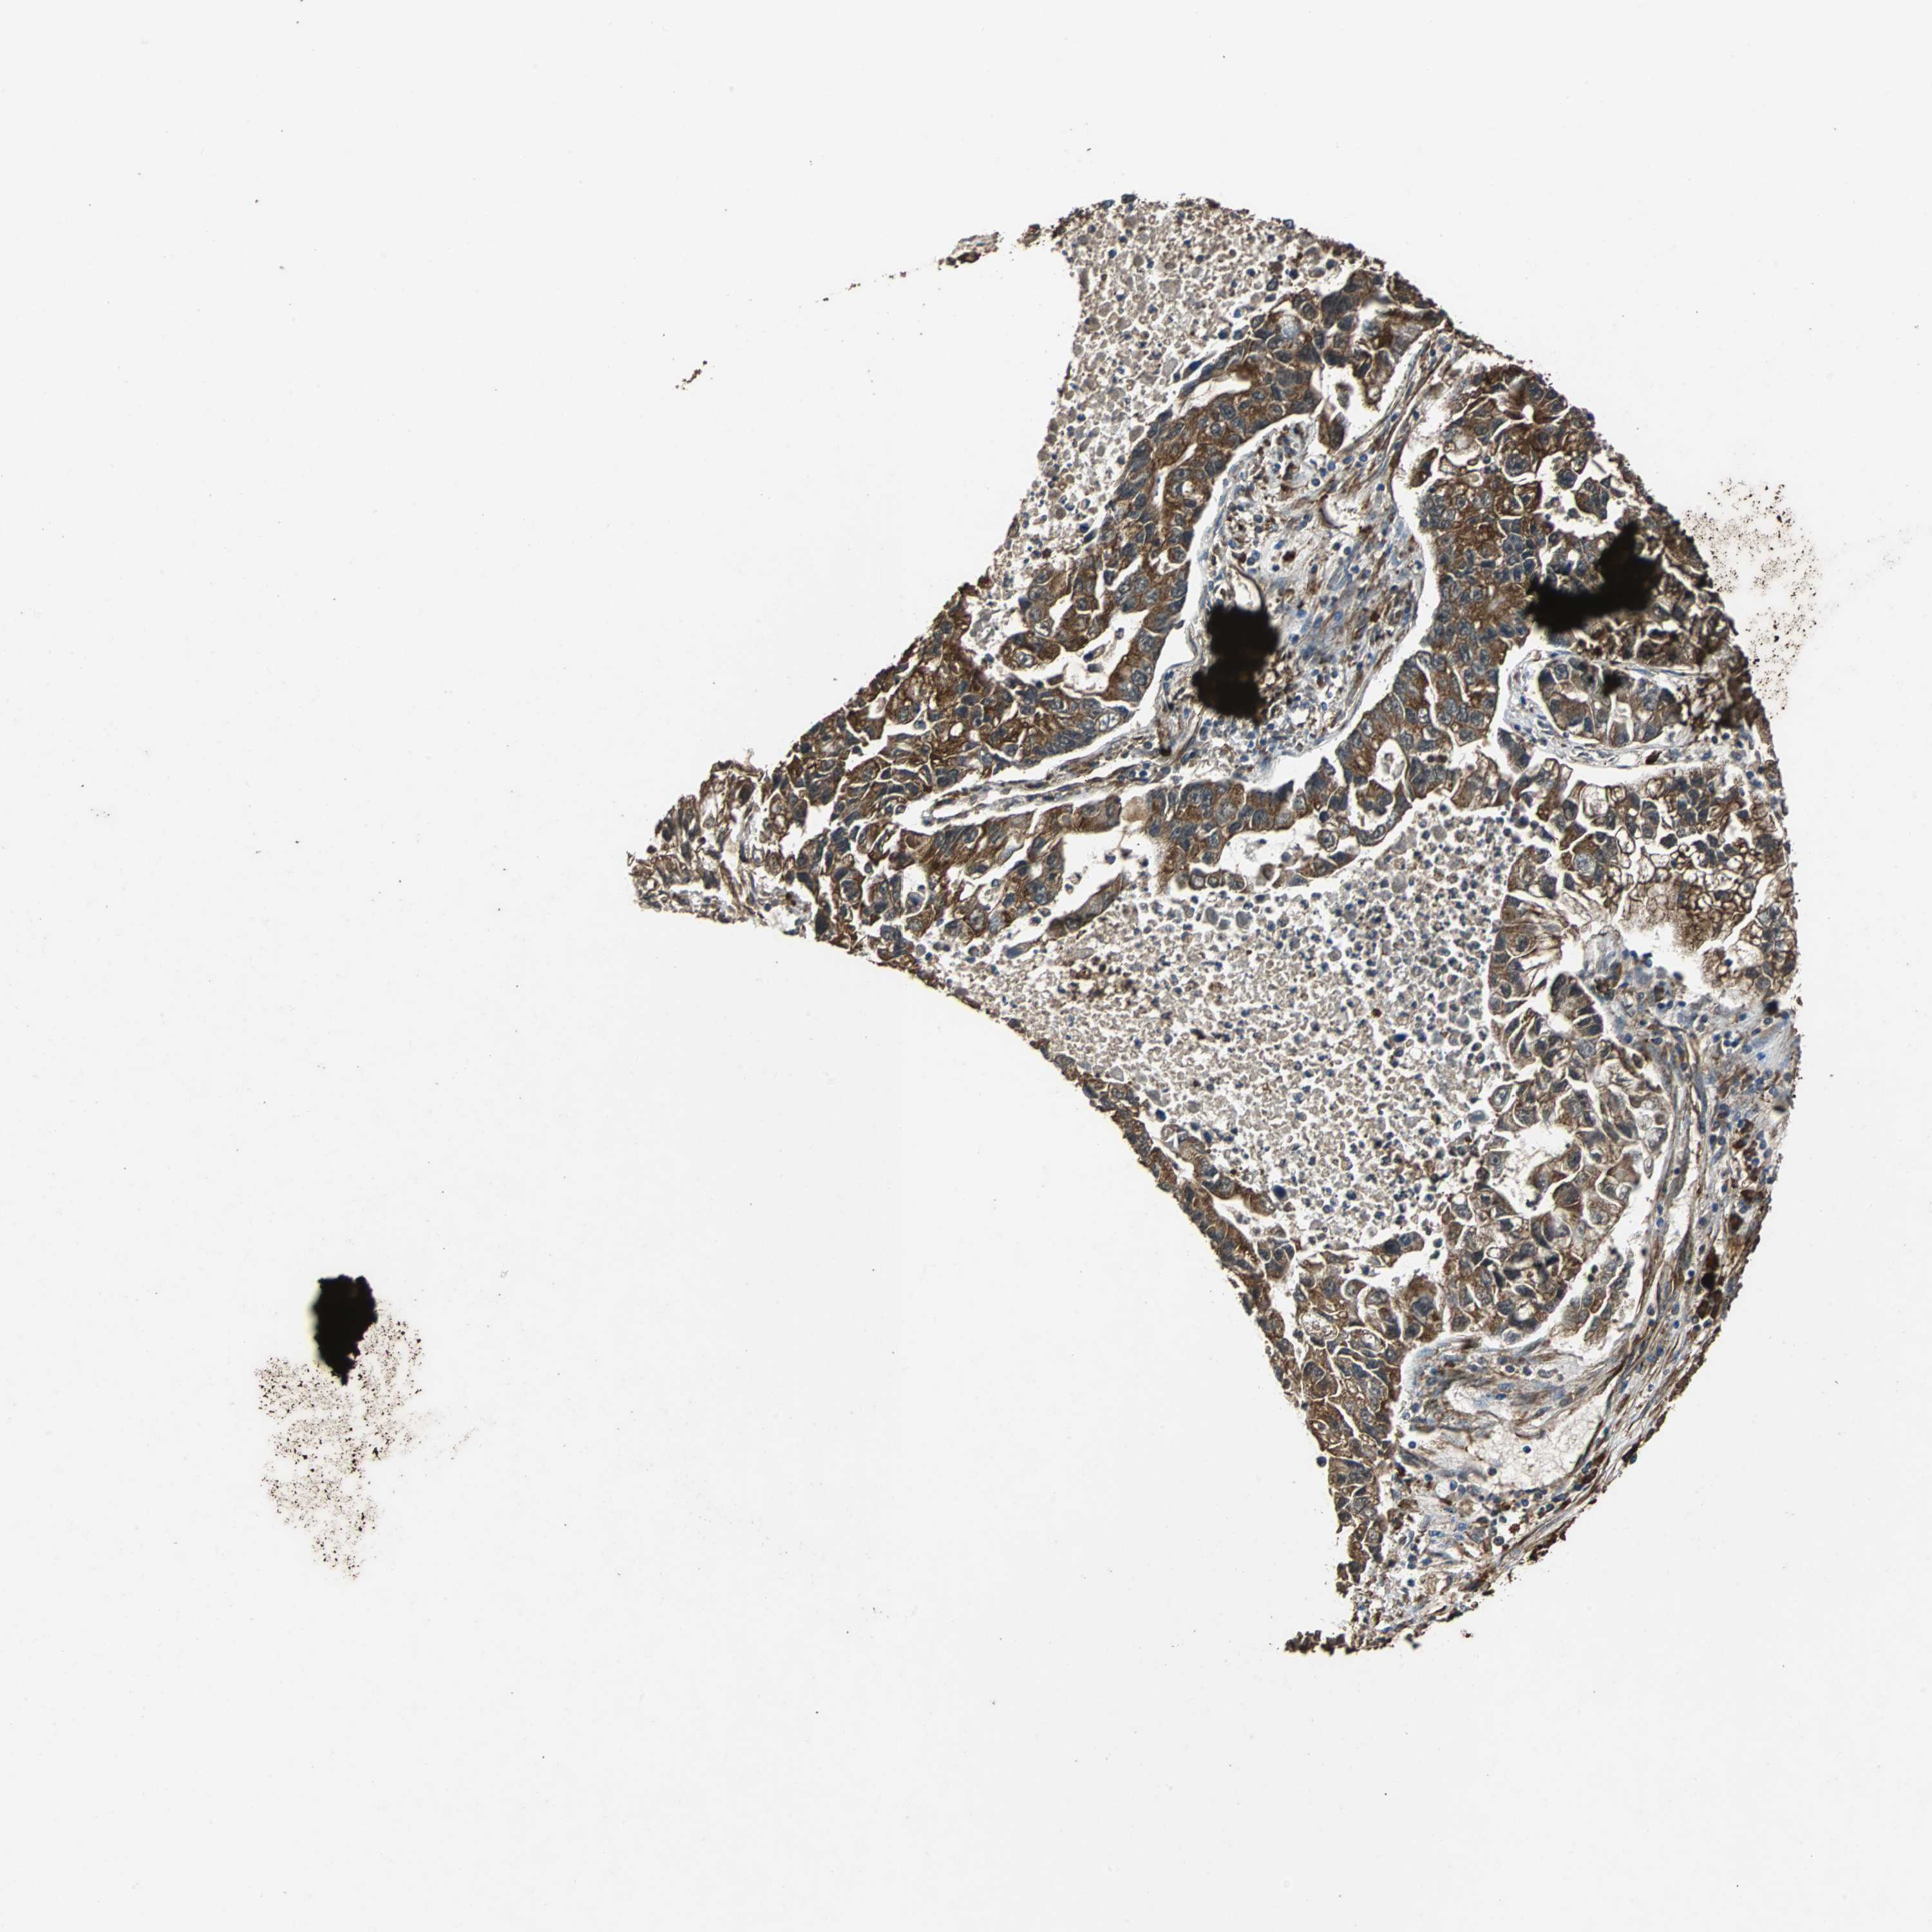

CANCER LUNG CANCER Show tissue menu

LUAD TCGA LUAD VALIDATION LUSC TCGA LUSC VALIDATION PROTEIN LUAD CPTAC PROTEIN LUSC CPTAC PROTEIN EXPRESSION

ANTIBODIES

AND

VALIDATION